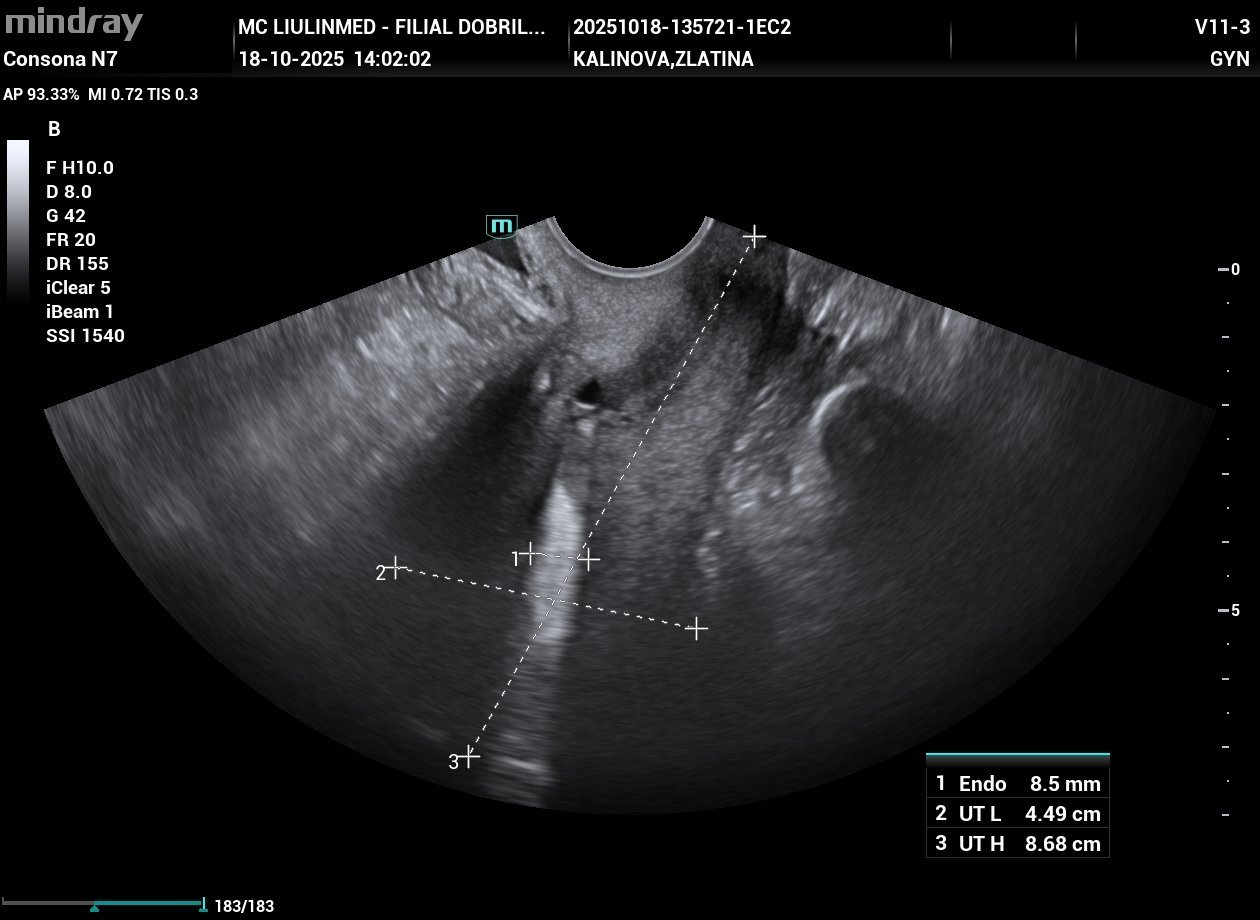

На първата снимка пише, че има един гестационен сак с размер 0,57 см. На втората снимка са яйчниците. На третата е измерена дебелината на ендометриума/маточната лигавица.

Значи, ако приемем, че става въпрос за бременност - на 16-18.09 зацапването може да е било менструация. С тези дати се връзва и размерът на гестационното сакче.